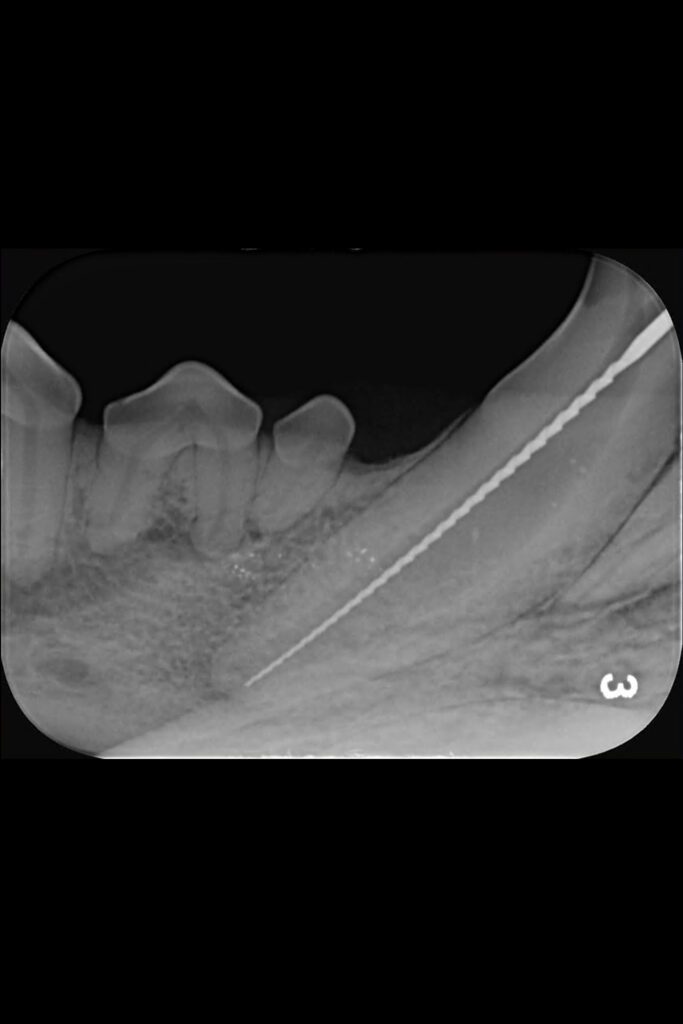

Initial radiographs were taken on our intraoral dental-specific X-ray unit to evaluate the dense tooth and bone structure. This revealed what was happening within the tooth and beneath the gumline – all the areas that cannot be seen with a visual examination. These showed not only the crown fracture but also a wide pulp chamber, which required root canal treatment.

A key part of this treatment involves inserting increasing file sizes into the tooth to reach the pulp to remove any infected or necrosed tissue. X-ray images are then again taken at various points throughout the procedure to check file size and position.